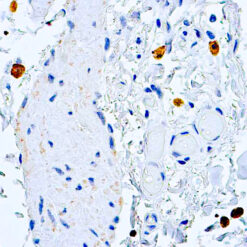

CD79a Antigen (HM47/A9)

This antibody is specific to human CD79a antigen complex, consisting of two polypeptides non-covalently associated with membrane-bound immunoglobulins on B cells. This complex of polypeptide and immunoglobulins constitute the B cell antigen receptor. The two components of this complex are designated CD79a and CD79b. The CD79a antigen appears at the pre-B cell stage, early in maturation and persists until the plasma cell stage. The CD79a antigen is found in majority of acute leukemias of precursor B cell type, in B cell lines and B cell lymphomas.

| Positive Control Tissue | Tonsil |